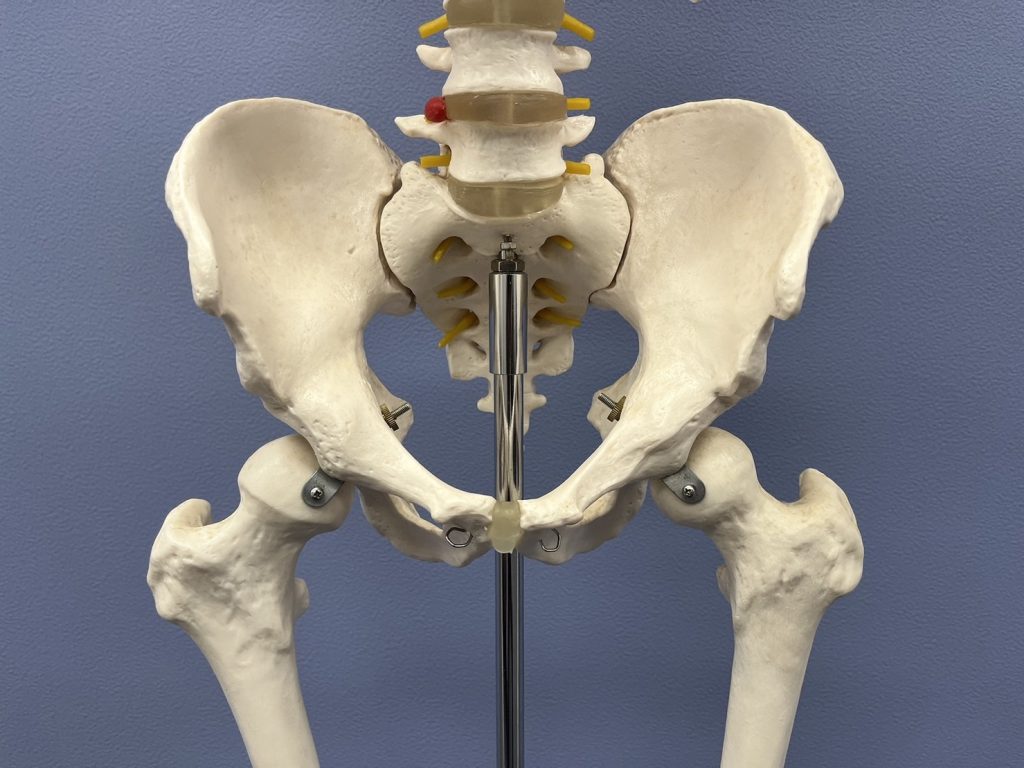

しかし、股関節を模型で確認すると、外側ではなく「中央」に位置していることが分かります。

つまり、股関節の本当の位置は「脚の付け根ラインの中央付近」になります。

体の奥にあることで、なかなかイメージしにくい股関節。